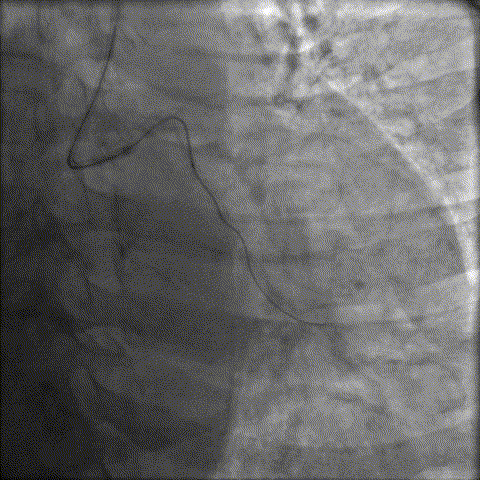

LAD近中段重度钙化伴迂曲,中段重度狭窄;LCX开口重度狭窄,近中段重度钙化,中段原支架完全闭塞

RCA近段及远段原支架重度再狭窄